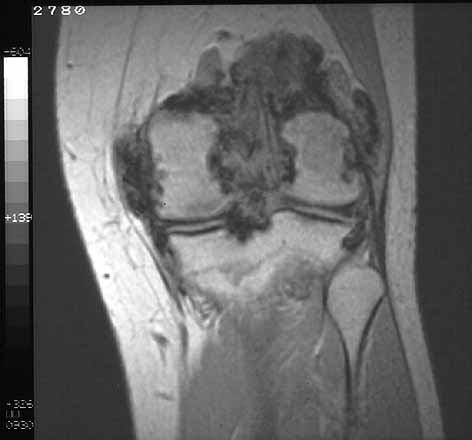

La Resonancia nuclear magnética aporta la información más característica en el diagnóstico diferencial entre alteraciones tumorales de partes blandas articulares (23), en la sinovitis villonodular pigmentada (24) . La RNM identifica hemosiderina, derrame articular e hiperplasia sinovial, sin destrucción significativa de la articulación. Además , permite detallar la extensión y distribución de la enfermedad en la articulación .(figuras 4 y 5 ).